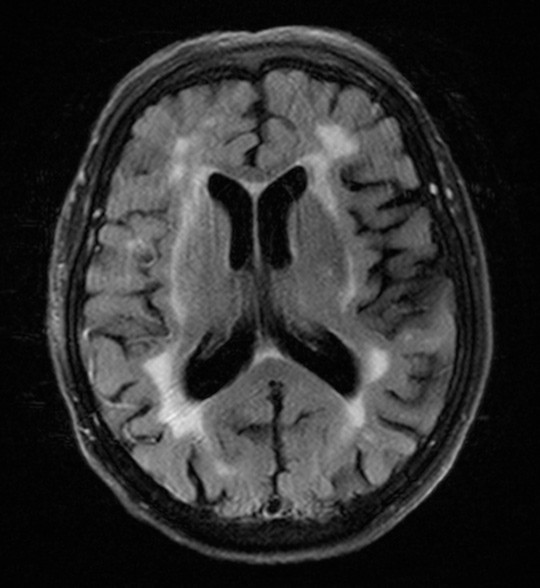

Pasienten hadde våknet med symptomene klokken 0625, og symptomdebut var ukjent. Det ble utført MR-caput etter oppvåkningsslag-protokoll («wake-up stroke») (DWI- og FLAIR-sekvens). Diffusjonsvektede bilder viste diffusjonsrestriksjon i høyre basalganglieregion og corona radiata (fig 1) med korrelerende lavsignal på ADC-kartet. FLAIR-sekvensen viste ingen sikre signalavvik i det affiserte området (fig 2). Dette tydet på at infarktforandringene var ferske, og klokken 0850 ble det derfor gitt intravenøs trombolytisk behandling. Etter at trombolytisk behandling var satt i gang ble det utført CT-angiografi av pre- og intracerebrale kar, som viste en okklusjon i proksimale del av arteria cerebri media (ACM) på høyre side. Pasienten ble raskt overflyttet til angiografilaben hvor det klokken 0940 ble igangsatt trombektomi, som var teknisk vellykket.

I dette tilfellet hadde man holdepunkter for at symptomene hadde startet innenfor trombolysegrensen på 4,5 timer, siden MR-undersøkelse viste iskemi på de diffusjonsvektede bildene, mens FLAIR-sekvensen ikke viste korrelerende signalavvik (diffusion-flair-mismatch). Rask diagnostikk bidro til at man kunne gi trombolytisk behandling og trombektomi, noe som trolig førte til et godt utfall for denne pasienten. Studier viser lovende resultater ved å identifisere de riktige pasientene for trombolytisk behandling, med bruk av MR etter oppvåkningsslagprotokoll (2).